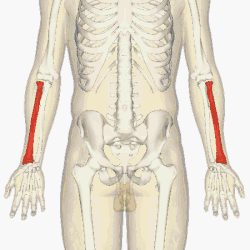

![]() The radius (shown in red) is a bone in the forearm. | |

Position of radius (shown in red).